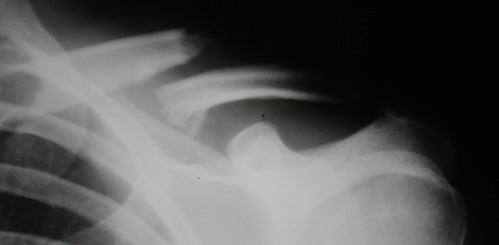

Один из вариантов, что удалось быстро найти, позже еще найду, но схема примерно такая (первое

вложение).

Мужик кочегар, срок нетрудоспособности 7 недель. Наружную конструкцию сняли через 3 недели. Далее без иммобилизации. Погруженную спицу можно убрать и через несколько месяцев, если жить не мешает.

Раньше не погружали, на рентгенограммах и натуре видно (последние 2 вложения). Как вариант спицы в периферическом отломке могут крепится на трехдырочную приставку, что дает возможность компрессии.